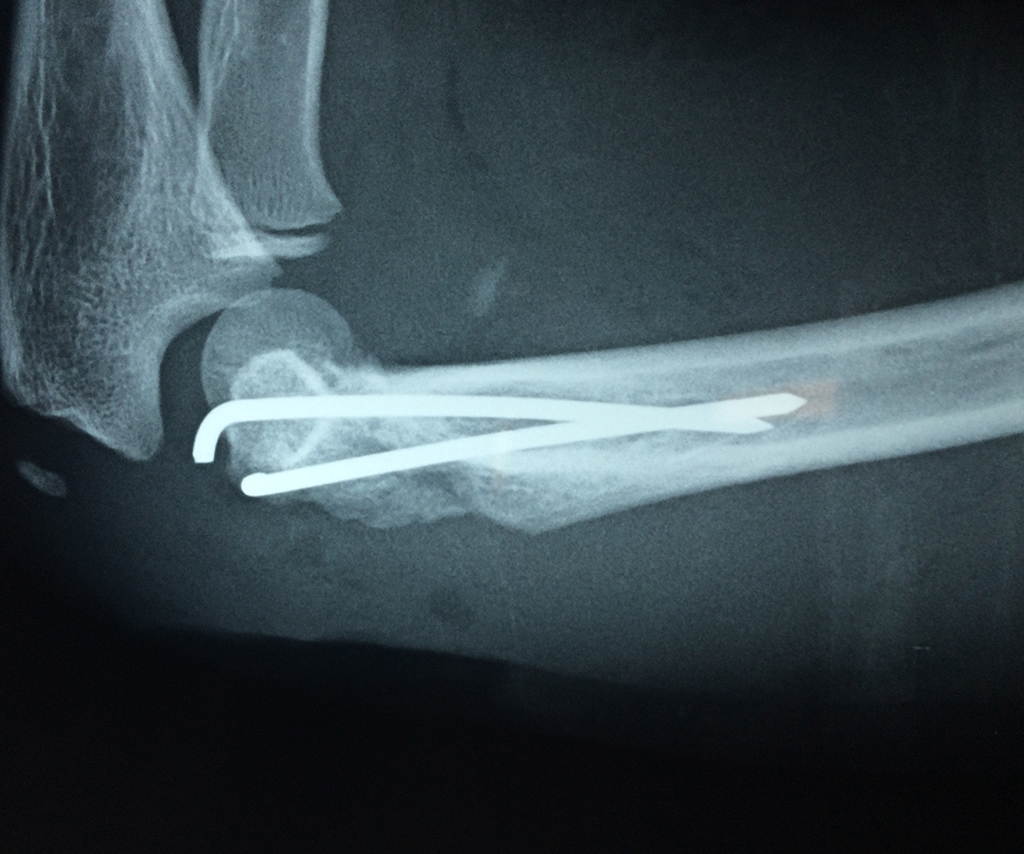

Húmero - Codo

En anatomía humana, la articulación del codo es la que une el brazo con el antebrazo, conectando la parte distal del hueso húmero con los extremos proximales de los huesos cúbito y radio.